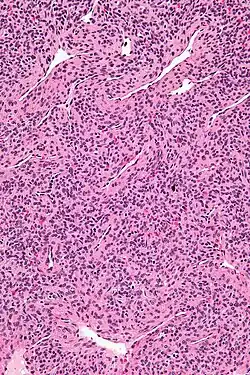

| Micrograph of a myopericytoma. H&E stain. | |

Myopericytoma is a rare perivascular soft tissue tumour. It is usually benign and typically in the distal extremities.[1]